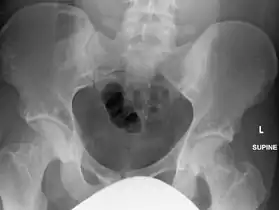

The radiographic appearance of osteopoikilosis on an X-ray is characterized by a pattern of numerous white densities of similar size spread throughout all the bones. This is a systemic condition. It must be differentiated from blastic metastasis, which can also present radiographically as white densities interspersed throughout bone. Blastic metastasis tends to present with larger and more irregular densities in less of a uniform pattern. Another differentiating factor is age, with blastic metastasis mostly affecting older people, and osteopoikilosis being found in people 20 years of age and younger.

In terms of the diagnosis Osteopoikilosis is radiographically evaluated via the presence of multiple symmetrical circular sclerotic opacities [2]

The distribution is variable, though it does not tend to affect the ribs, spine, or skull.[3]